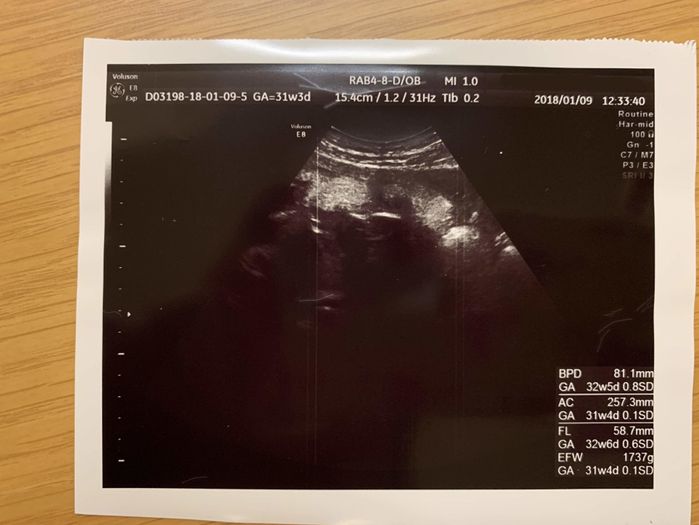

妊娠31週目 マタニティフォトで最後の妊娠を家族で記念撮影

妊娠31週目の健診では、赤ちゃんは推定体重1737gまで順調に成長。おなかが急速に大きくなり、行き場をなくした胃が押し上げられ、後期つわり(逆流性食道炎の症状)も激しくなってきたころです。エコーの赤ちゃんも窮屈そう。そして、妊娠9ヶ月に入ると、家族4人でマタニティフォトを撮りに行きました。もう少しで5人家族になるんだと思うと、なんだか不思議な気持ちでした。予定日まであと1ヶ月ほど。妊娠35週目から産休に入ります。これまでできなかった出産の準備を始めようと、あれこれ考えていました。